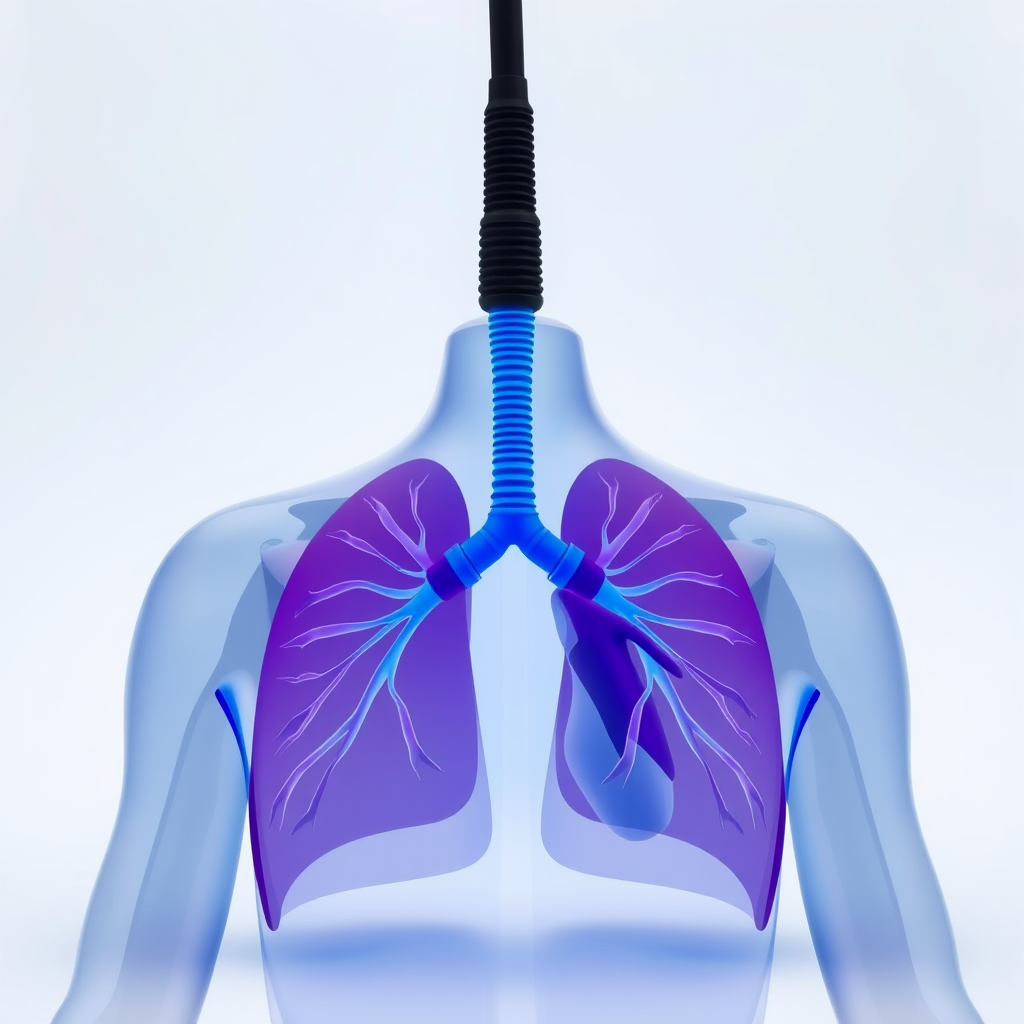

Fisioterapia Cardiorrespiratória no Ipiranga: Benefícios para Saúde e Bem-Estar

A fisioterapia cardiorrespiratória no Ipiranga oferece uma série de benefícios que contribuem para a saúde e o bem-estar dos pacientes.

Esse tratamento é indicado para pessoas que enfrentam condições respiratórias e cardiovasculares.

A fisioterapia cardiorrespiratória no Ipiranga auxilia na expansão da capacidade pulmonar.

Isso é essencial para pacientes com doenças respiratórias crônicas.

A fisioterapia cardiorrespiratória no Ipiranga auxilia no controle de sintomas como falta de ar e tosse.